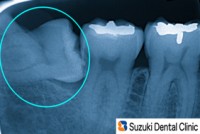

抜歯あとのケアーには、鈴木歯科医院のパターン、「溶ける糸」と「テルプラグ」の使用です。

「溶ける糸」の特長は、抜糸のために後日、わざわざ来院する必要はありません。

また「テルプラグ(コラーゲンの塊)」の使用目的は、抜歯後の痛みの軽減と生じた穴を、早期に回復してくれることが特長です。

優れた材料ですが、いずれも特に別途料金はいただいていませんので、ご安心ください。

右:術後